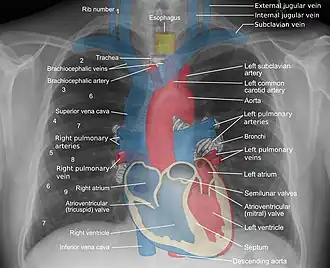

Mediastinal structures on a chest radiograph.

In the average person, the diaphragm should be intersected by the 5th to 7th anterior ribs at the mid-clavicular line, and 9 to 10 posterior ribs should be viewable on a normal PA inspiratory film. An increase in the number of viewable ribs implies hyperinflation, as can occur, for example, with obstructive lung disease or foreign body aspiration. A decrease implies hypoventilation, as can occur with restrictive lung disease, pleural effusions or atelectasis. Underexpansion can also cause interstitial markings due to parenchymal crowding, which can mimic the appearance of interstitial lung disease. Enlargement of the right descending pulmonary artery can indirectly reflect changes of pulmonary hypertension, with a size greater than 16 mm abnormal in men and 15 mm in women.[6]

Appropriate penetration of the film can be assessed by faint visualization of the thoracic spines and lung markings behind the heart. The right diaphragm is usually higher than the left, with the liver being situated beneath it in the abdomen. The minor fissure can sometimes be seen on the right as a thin horizontal line at the level of the fifth or sixth rib. Splaying of the carina can also suggest a tumor or process in the middle mediastinum or enlargement of the left atrium, with a normal angle of approximately 60 degrees. The right paratracheal stripe is also important to assess, as it can reflect a process in the posterior mediastinum, in particular the spine or paraspinal soft tissues; normally it should measure 3 mm or less. The left paratracheal stripe is more variable and only seen in 25% of normal patients on posteroanterior views.[7]

Localization of lesions or inflammatory and infectious processes can be difficult to discern on chest radiograph, but can be inferred by silhouetting and the hilum overlay sign with adjacent structures. If either hemidiaphragm is blurred, for example, this suggests the lesion to be from the corresponding lower lobe. If the right heart border is blurred, than the pathology is likely in the right middle lobe, though a cavum deformity can also blur the right heard border due to indentation of the adjacent sternum. If the left heart border is blurred, this implies a process at the lingula.[8]